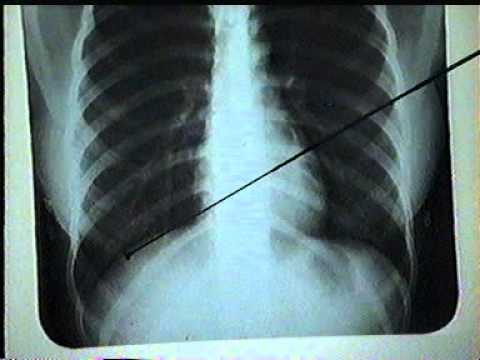

Hình ảnh cho bệnh ung thư phổi

Hình ảnh cho bệnh ung thư phổi giúp mọi người hình dung một cách chân thực và chính xác về một trong những căn bệnh ung thư phổ biến và có tỷ lệ tử vong cao nhất. Bệnh ung thư phổi có nhiều giai đoạn khác nhau. Mỗi giai đoạn, lá phổi lại có những đặc điểm nhất định.

Hình ảnh cho bệnh ung thư phổi qua mô phỏng

Hình ảnh bệnh ung thư phổi qua từng giai đoạn